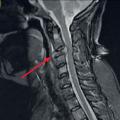

Mammographie et échographie des seins et des creux axillaires sont fondamentales pour le diagnostic et la caractérisation morphologique. Les anomalies retrouvées sont uniquement mammographiques dans le cas particulier de foyer de microcalcifications (isolé ou étendu dans le sein ; fig. 1) ou seulement échographiques en cas de nodule tissulaire ; dans la majorité des cas, le cancer est vu à l’écho et à la mammographie. Les régions axillaires sont systématiquement analysées avec les 2 techniques.

En cas de diagnostic positif, on recherche à l’interrogatoire des symptômes d’apparition récente : fatigue, amaigrissement, douleur osseuse élective, insomniante, non calmée par des antalgiques simples (fig. 2 ; métastase osseuse avec risque neurologique par lyse complète de C3). Plus rarement, la patiente se plaint d’un essoufflement, un ptosis (syndrome paranéoplasique), une distension abdominale (ascite et localisation péritonéale).